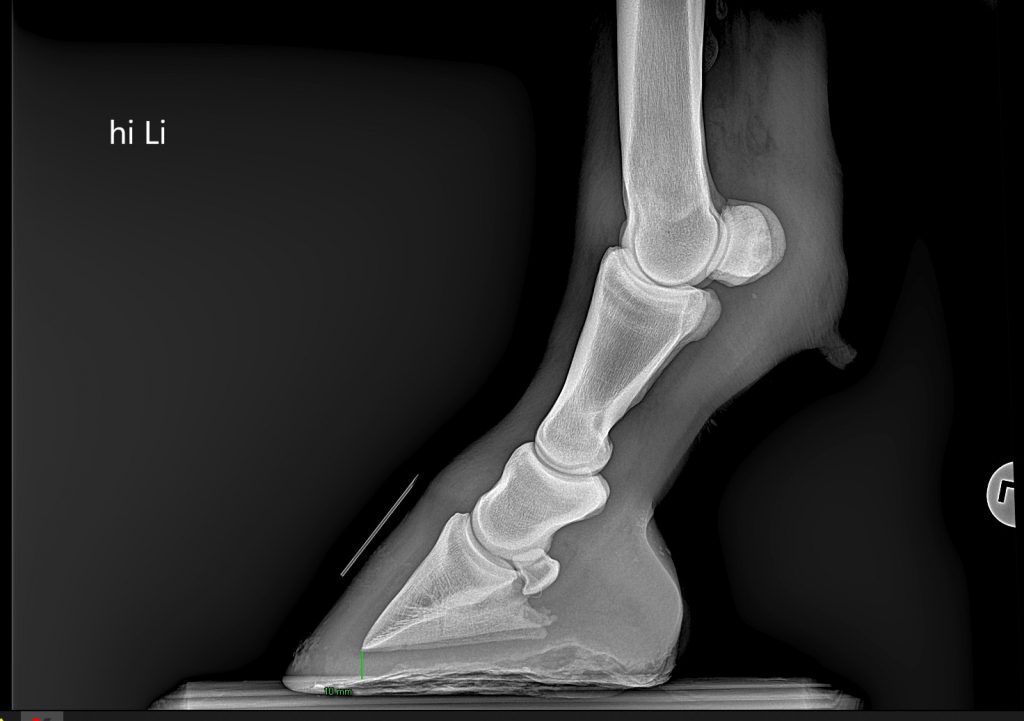

Podologie (im Aufbau )